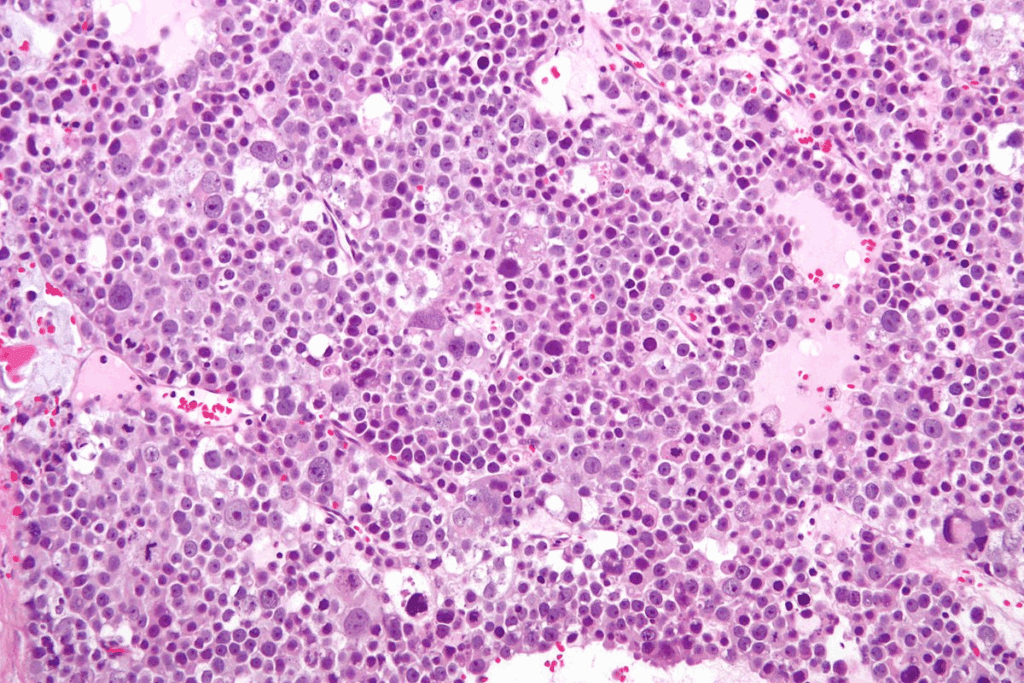

Bone Marrow Biopsy and Aspiration

A bone marrow biopsy and aspiration are key for diagnosing bone marrow diseases. These tests take a bone marrow sample for study. The biopsy looks at the bone marrow’s structure, and aspiration checks the cells.